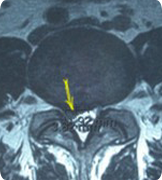

磁振造影檢橫切面 可見突出的椎間盤,向後下方位移至第五 腰椎體後方

吳先生的MRI顯示嚴重的椎間盤突出及神經根壓迫